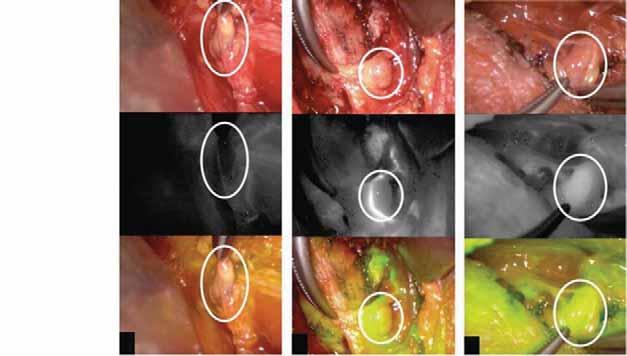

Widok

Widok w podczerwieni

Minimalnie inwazyjna wideoskopowa tyreoidektomia minimally invasive video-assisted thyroidectomy

Rycina 76.15.

Rycina 76.16.